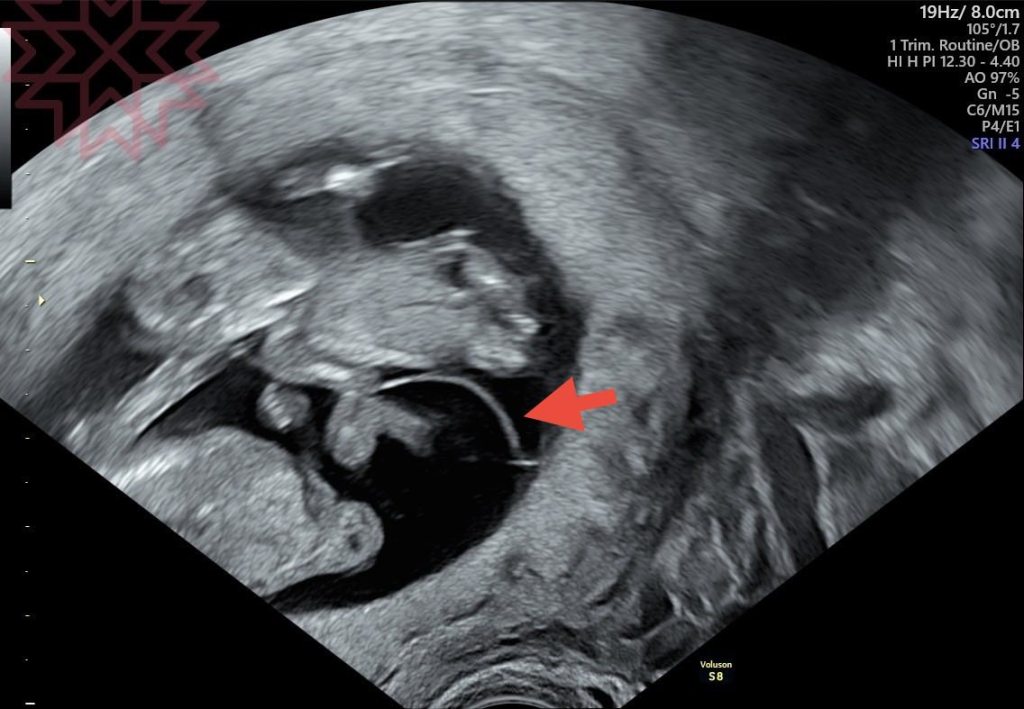

這位媽咪在這個星期二

真的就從台南上來台中找我

結果

答案大概五秒鐘就確認了

就在最後一張圖